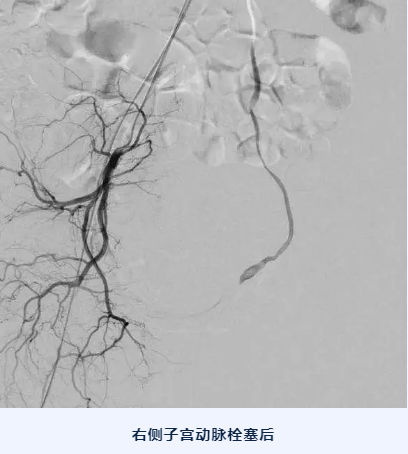

针对此类病情,北京燕化医院运用多学科联动模式,采用子宫动脉介入栓塞的技术,阻断出血的风险,然后在彩超的监视下行清宫术。血管介入科大夫在患者腹股沟处取一个1厘米长的小切口,由此进入导丝游走到子宫动脉血管处,打入栓塞剂,堵塞血管。紧接着,在麻醉科及B超室的密切配合下,妇科医生再行清宫术。术后恢复快,身体上也就一个极小伤口。